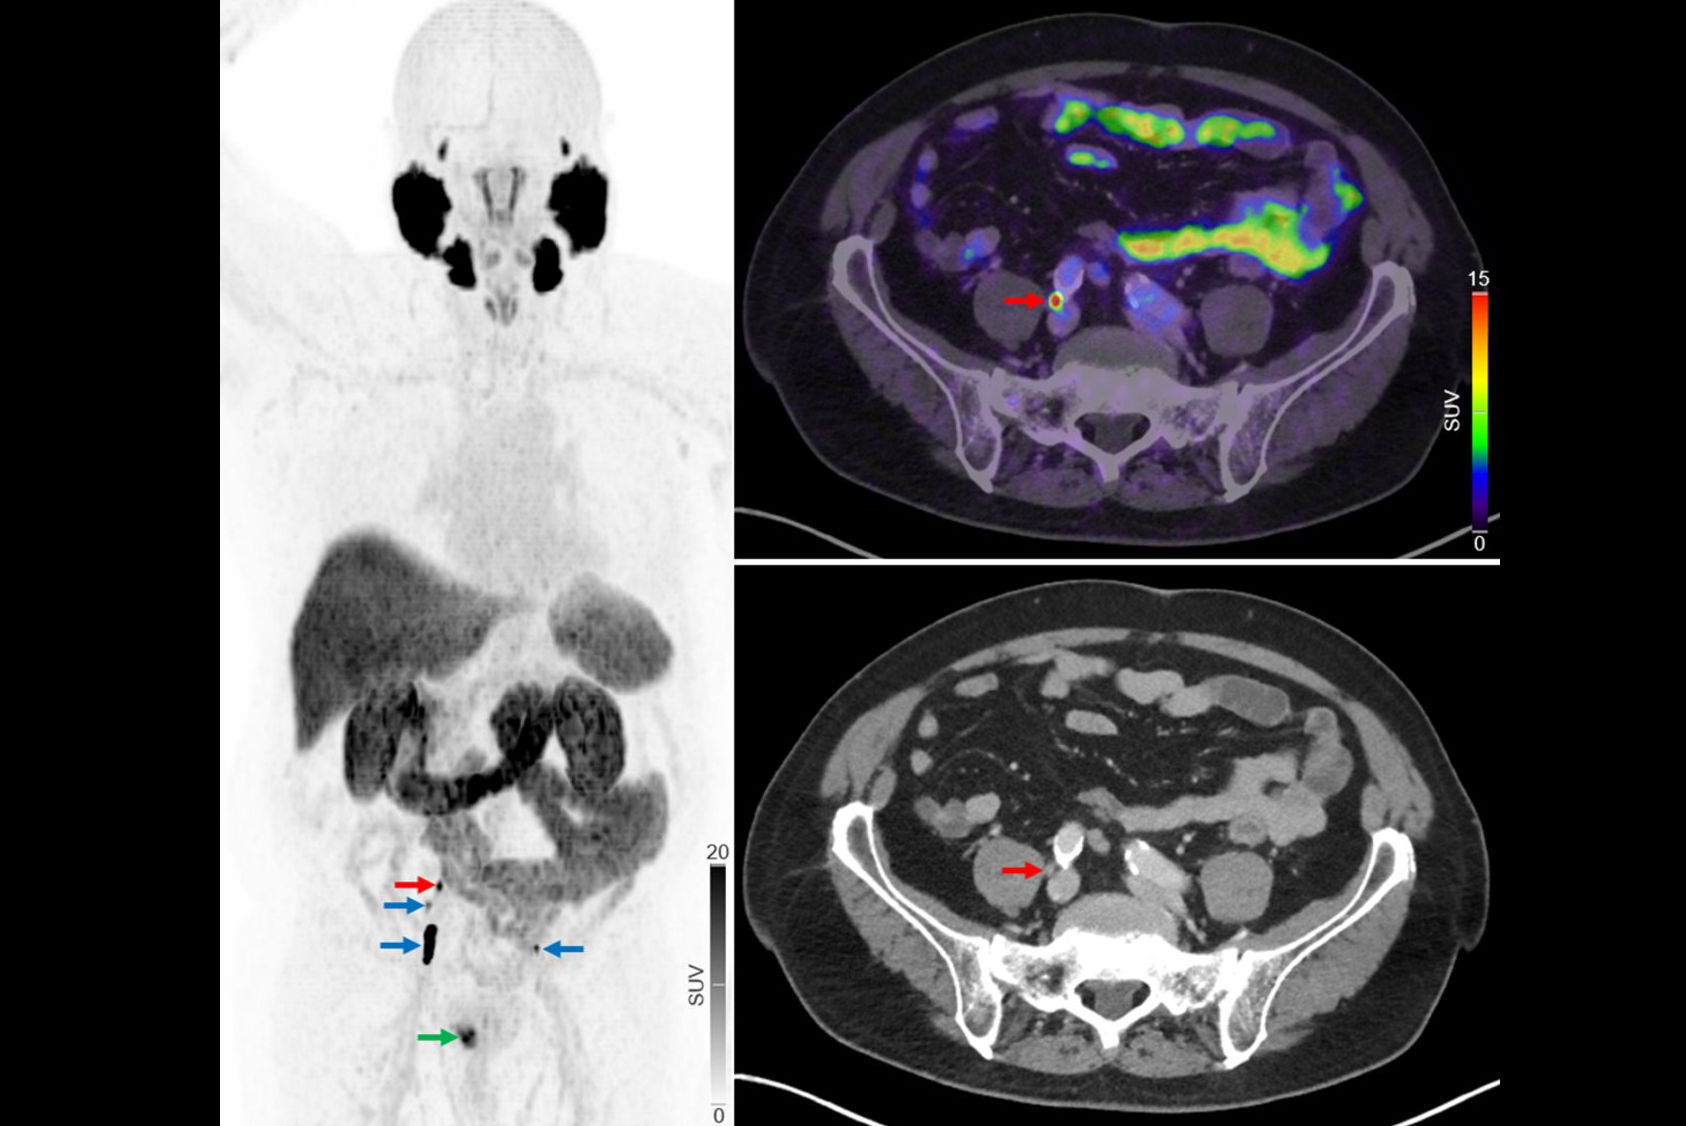

Namely, individuals receiving theranostic treatments not only receive therapeutic drugs but also radiotracer injections and undergo multiple PET scans and dosimetry imaging, which involves multi-timepoint SPECT scans. Add typical labs for oncology, and all of this adds up, Bradshaw said.

“Just as we're starting to tackle things like SUV values [standard uptake values] and trying to harmonize and standardize that from one system to another for diagnostic purposes, now we have this huge new challenge with theranostics where we now need to keep track in some way of the treatments that we're giving to patients and to try and quantify the responses to those treatments,” Siegel said.

Also, initial efforts are underway toward appropriate DICOM usage for nuclear medicine theranostics imaging and dosimetry data, and standardization of other metadata, such as radioactivity meter calibrations, PET and SPECT calibration, and imaging and dosimetry workflows, Siegel noted.